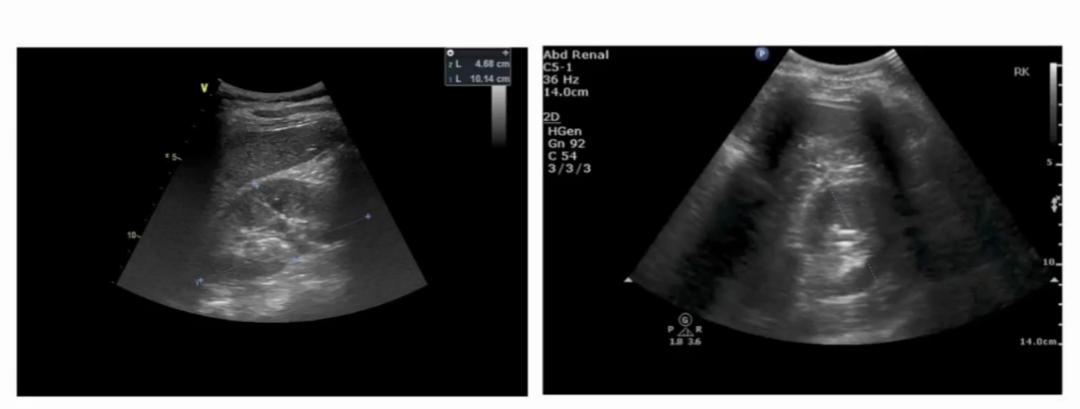

1.2个基本切面

包括最大的长轴(冠状)切面与短轴(水平)切面。

长轴切面超声图(左)、短轴切面超声图(右)